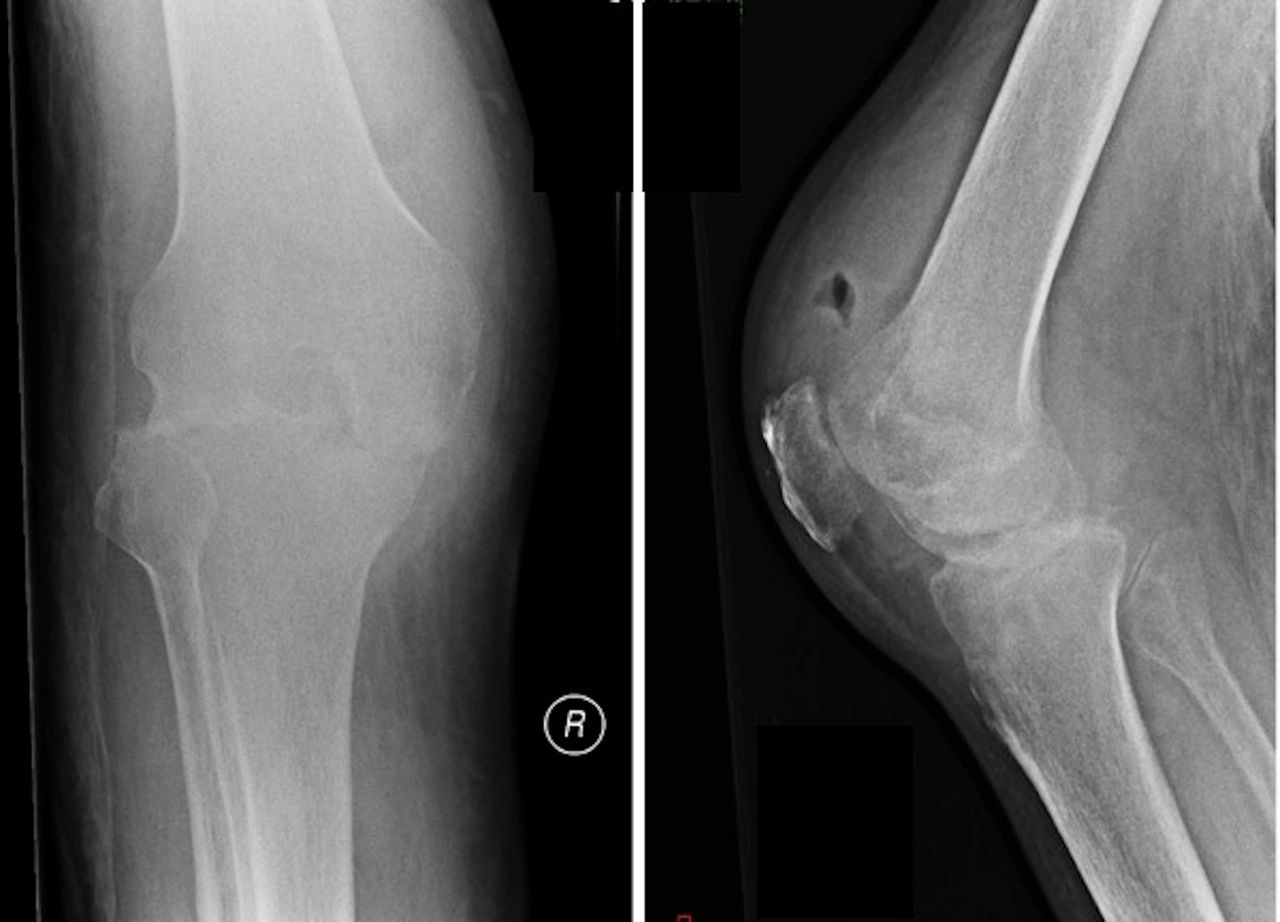

Septic Arthritis

Source: BMJ Case Reports

Where osteoarthritis will cause joint space narrowing based on biomechanical pressures, generally resulting in one compartment being more affected than another, septic arthropathy will attack all articular surfaces within the affected joint simultaneously resulting in a more uniform distribution of joint space narrowing. Another feature is rapid progression, over weeks or months. Eventually, there will be destruction and collapse of the subchondral bone.

That said, septic arthropathy has quite specific clinical features and arthrocentesis is the proper objective test to make the diagnosis. Radiographs may demonstrate the effusion and the bony changes but, given that images may appear normal in the first couple of weeks after onset, negative imaging does not exclude septic arthropathy.

The role of imaging is to help exclude other potential causes of a red, hot, swollen joint, such as gout (look for tophi or mechanical erosions) or inflammatory arthropathy (look for juxta-articular osteopenia and erosions at the insertion of the joint capsule(bare area erosions)). Imaging findings (also involving MRI, for preference) would only form the basis of diagnosis if the joint is not able to be aspirated.